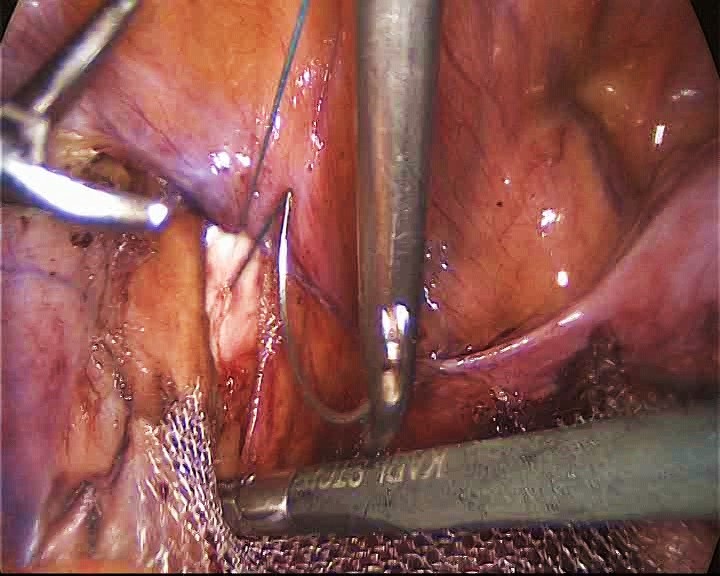

Первый имплантат продольной формы с выступами крепили продольно широким основанием в ректовагинальное пространство (рис. 1), с фиксацией отдельными швами нерассасывающейся нитью к пучкам мышц, поднимающих задний проход с обеих сторон (рис. 2), а узким проксимальным основанием к культе влагалища или шейки матки.

Рис. 1. Первый имплантат продольной формы с выступами располагают продольно широким основанием в ректовагинальное пространство.

Fig. 1. The first longitudinal-shaped implant with protrusions is placed longitudinally with a wide base into the rectovaginal space.